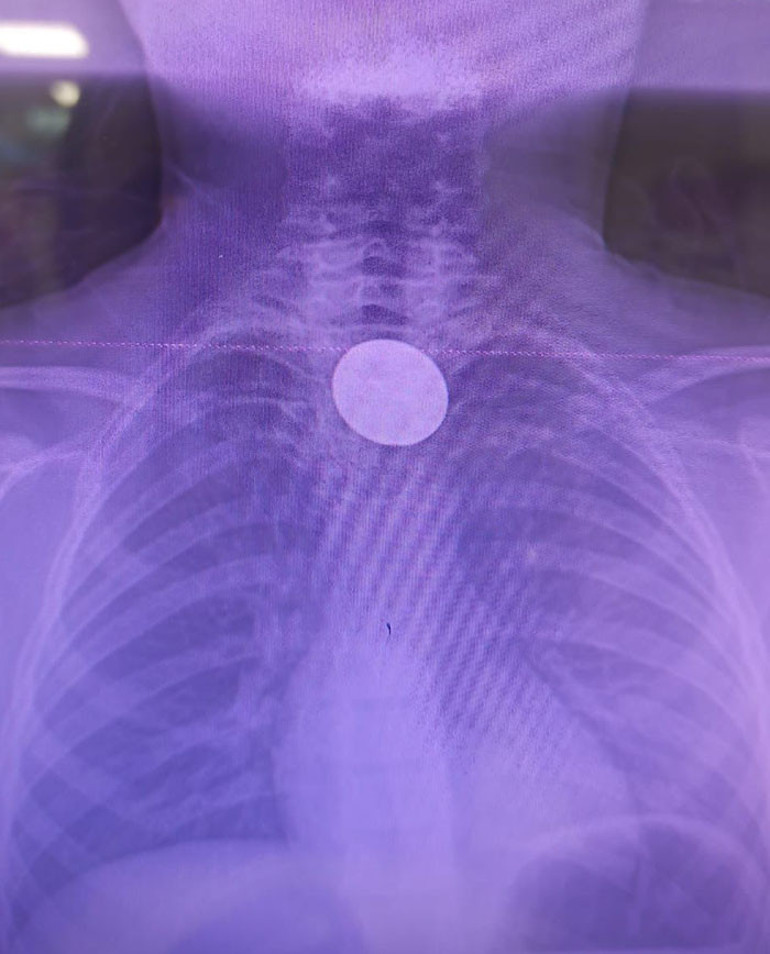

Siirt Eğitim ve Araştırma Hastanesi'nden gelen bilgilere göre, boğazında madeni para sıkışan 8 yaşındaki Y.K, ailesi tarafından hastaneye götürüldü.

Hastanede yapılan incelemeler sonucunda çocuğun boğazında yer alan madeni para, Gastroenteroloji Uzmanı Dr. Yaren Dirik ve Kulak Burun Boğaz Doktoru Dr. Yasin Gökçınar tarafından gerçekleştirilen bir operasyonla başarıyla alındı.